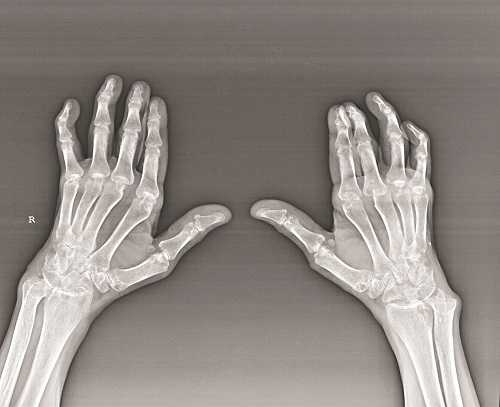

Biến chứng của VKDT là gây co quắp các ngón tay

Xét nghiệm sẽ thấy tốc độ máu lắng, tỉ lệ CRP (C- Reactive Protein) tăng cao, đặc biệt là yếu tố dạng thấp RF (Rheumatoid Factor) dương tính. Chụp X-quang thấy có hình ảnh biến đổi xương (mất vôi, hình dải hoặc xói mòn hoặc khuyết xương hoặc hẹp khe khớp hoặc dính khớp.

Chụp X-quang thấy có hình ảnh biến đổi xương